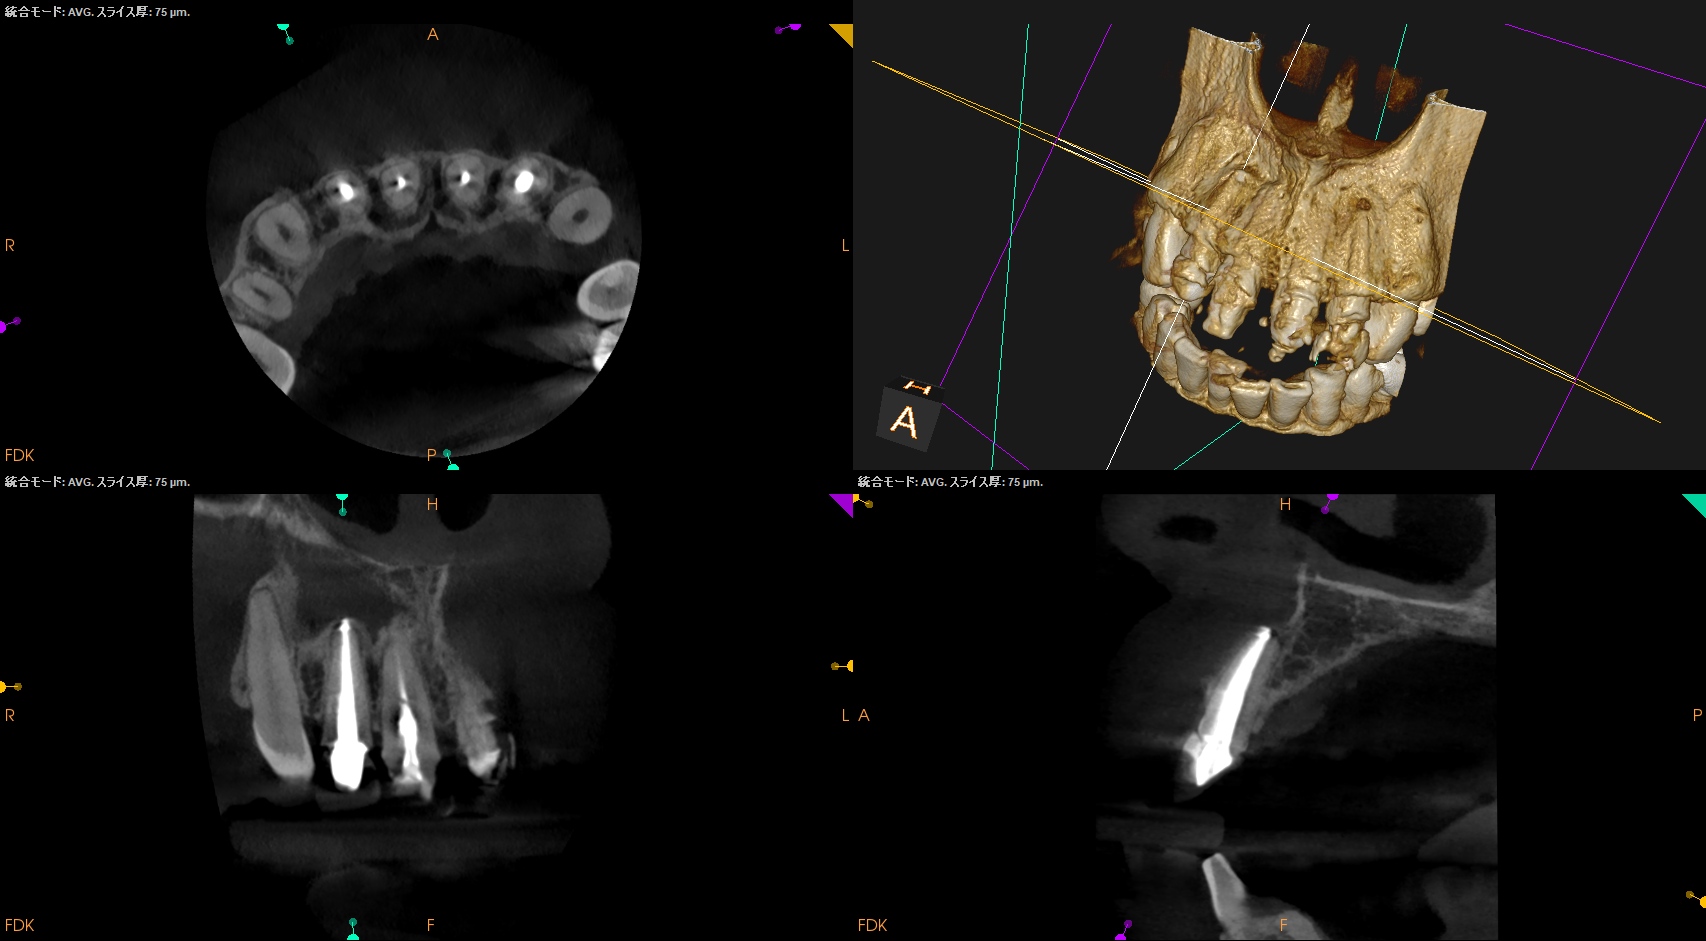

ここから9ヶ月が経過し、かかりつけ医の先生からCBCTを評価してほしいとの依頼があった。

その結果が以下である。

#7

#10

さてこの画像からあなたは治癒傾向であるか否か?を判断できるであろうか?

そう。

よくわからないのである。

なので、実際に当歯科医院で検査も含めて評価することになった。